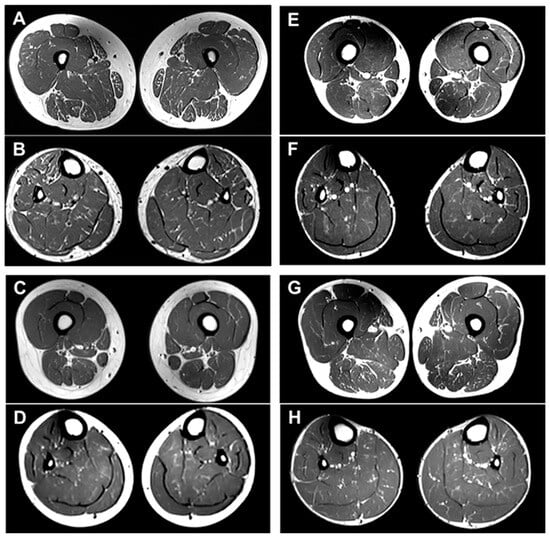

2.5. MRI Features of the Brain and Lower Extremity

4.6. Brain and Lower Extremity MRI

- Kim, H.S.; Kim, H.J.; Nam, S.H.; Kim, S.B.; Choi, Y.J.; Lee, K.S.; Chung, K.W.; Yoon, Y.C.; Choi, B.O. Clinical and neuroimaging features in Charcot-Marie-Tooth patients with GDAP1 mutations. J. Clin. Neurol. 2021, 17, 52–62. [Google Scholar] [CrossRef] [PubMed]

- Kwon, H.M.; Kim, H.S.; Kim, S.B.; Park, J.H.; Nam, D.E.; Lee, A.J.; Nam, S.H.; Hwang, S.; Chung, K.W.; Choi, B.O. Clinical and neuroimaging features in Charcot-Marie-Tooth patients with GNB4 mutations. Life 2021, 11, 494. [Google Scholar] [CrossRef] [PubMed]